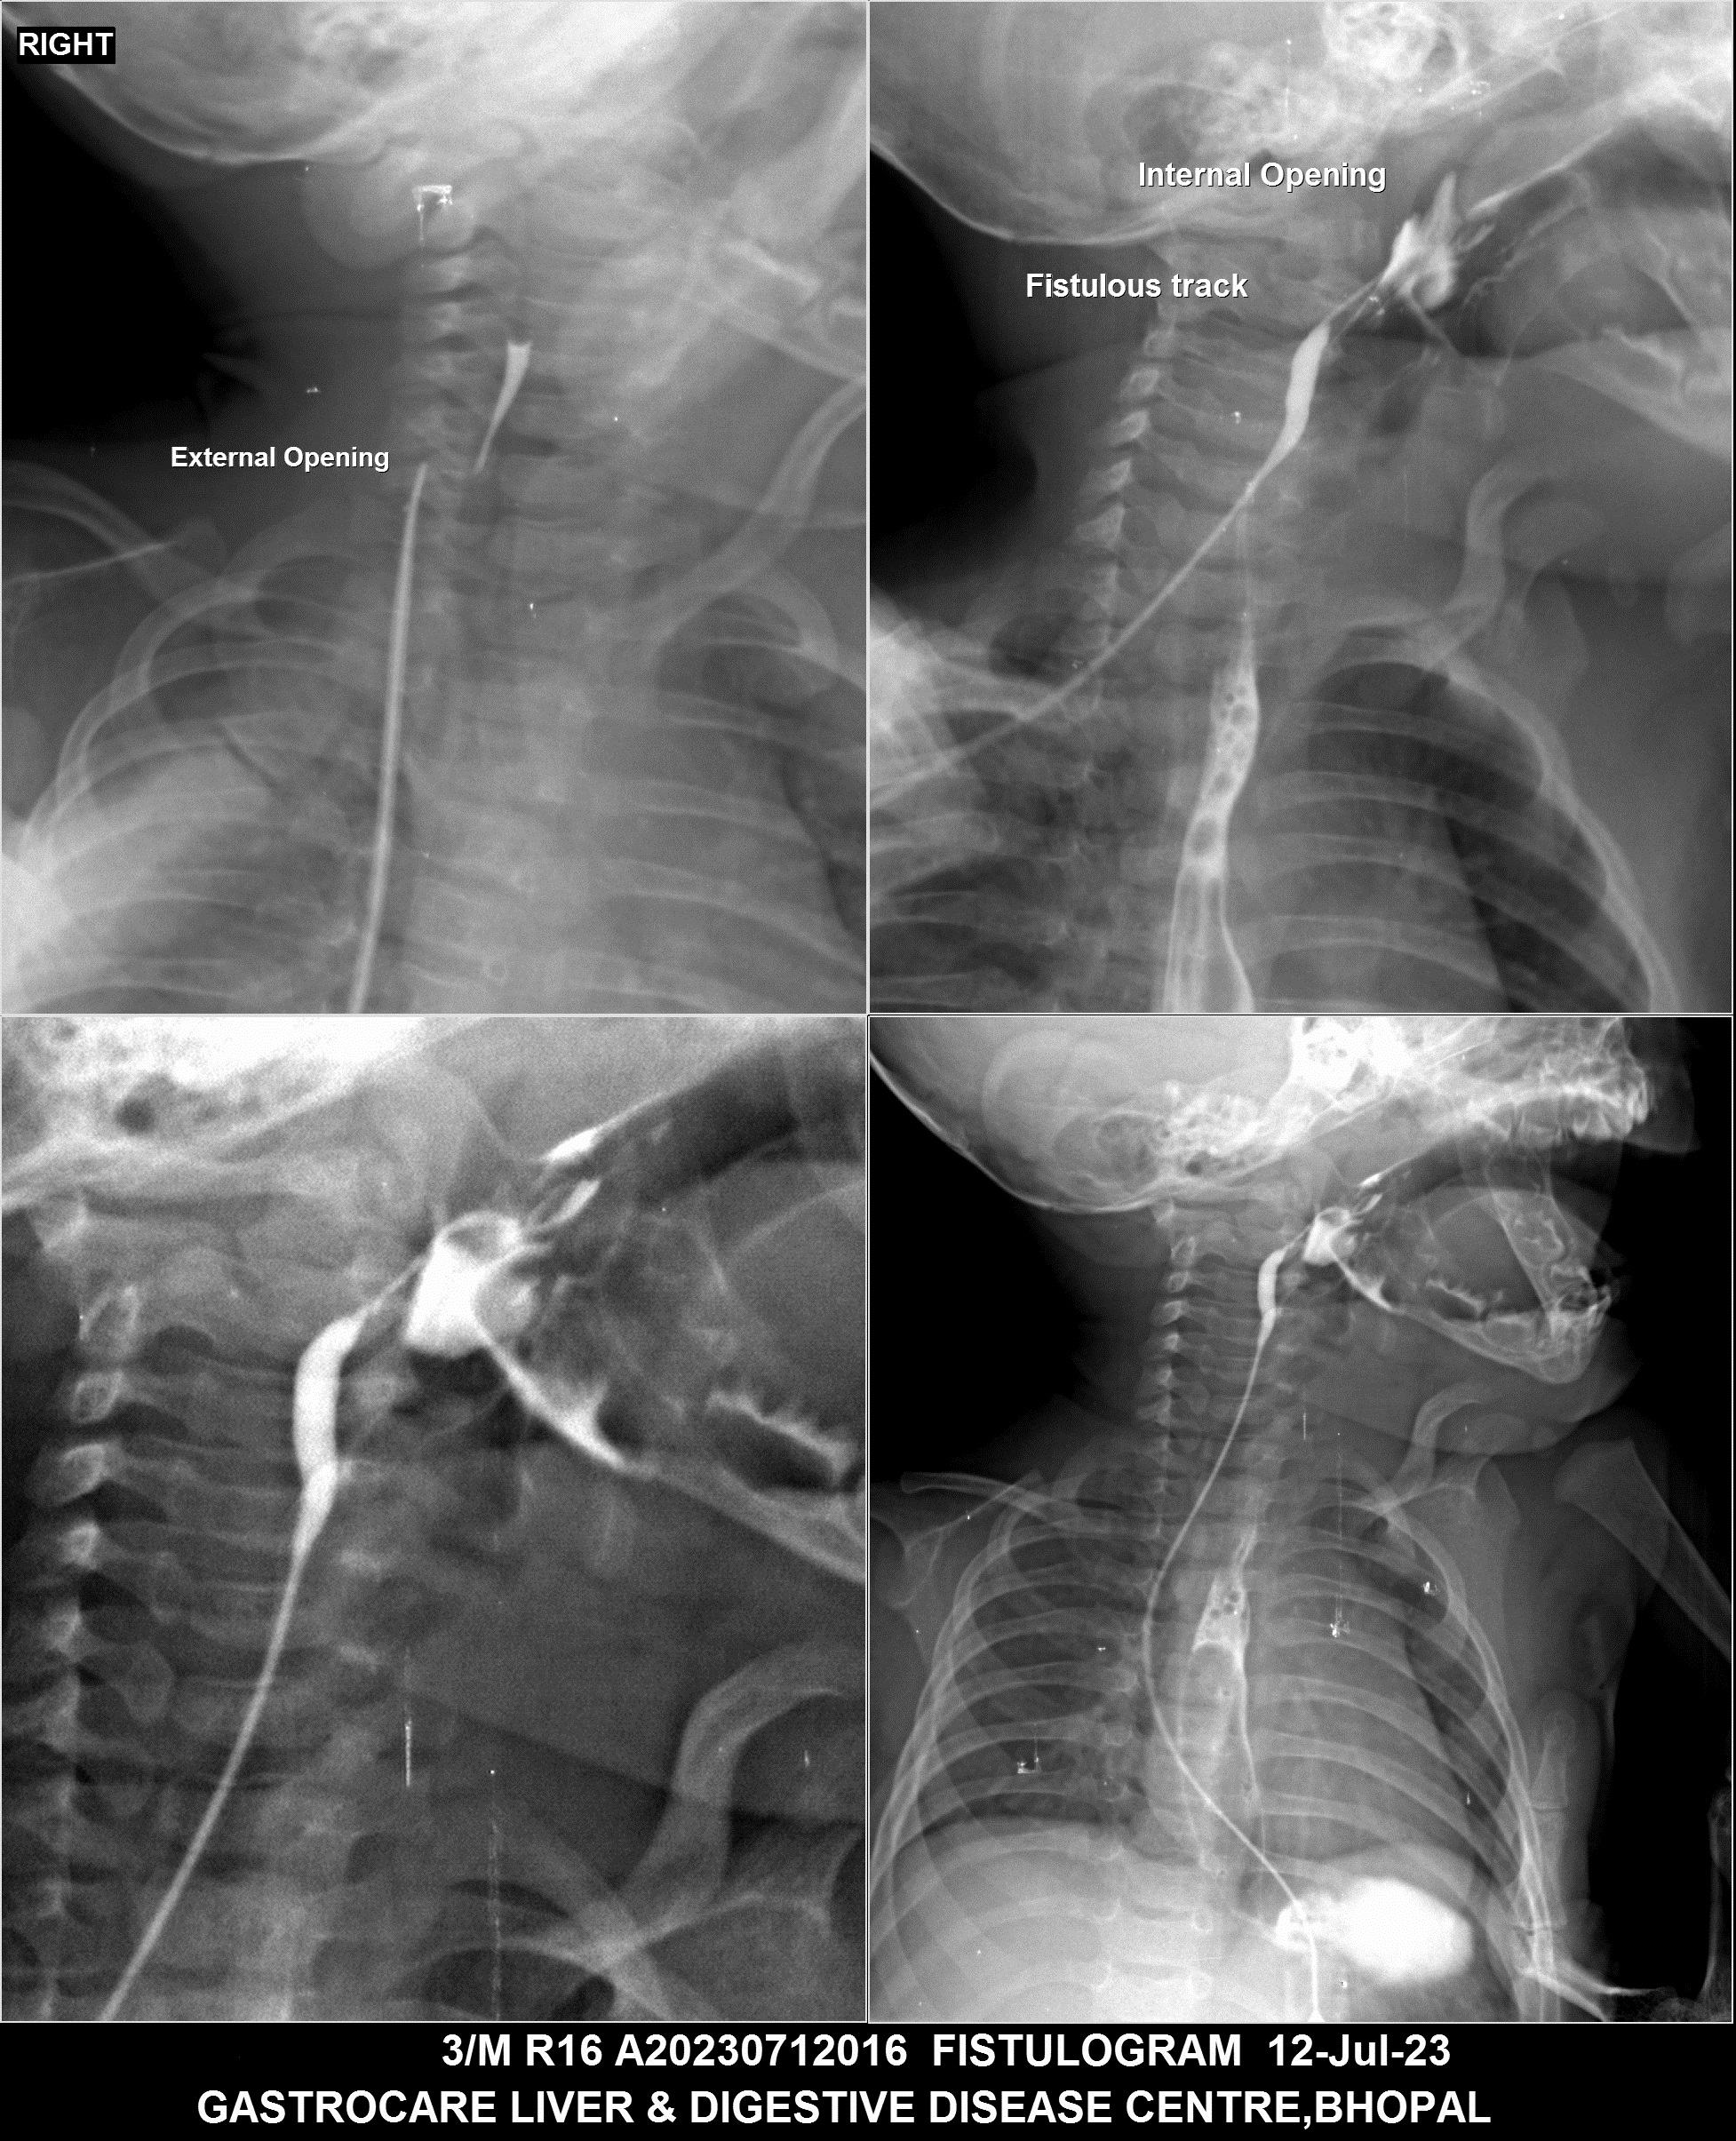

Section: FISTULOGRAM Total: 8 images

BaM Enteroclysis Loopogram BaE Fistulogram Urethrogram HSG